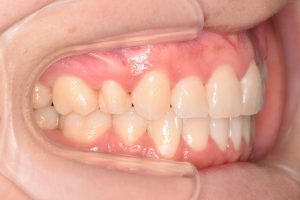

初診時(2022年12月)と装置撤去時(2025年9月)の写真です。

右側

犬歯を咬合に参加させることで

奥歯に負担が掛からなくなります。

(犬歯誘導)